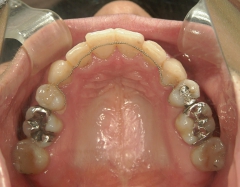

矯正歯科 治療前矯正歯科 治療前

矯正歯科 治療前 上下左右4番 計4本を抜歯して叢生を改善しました。

矯正_灰色.pngno.31_1962_治療前_上.JPG矯正_灰色.png